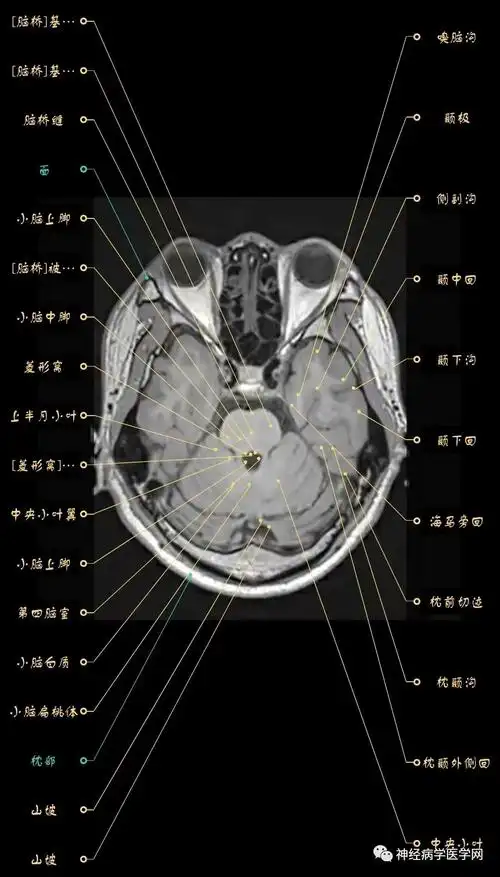

正常脑组织磁共振信号特点.##关注我每天坚持分享知识 #医者 - 抖音